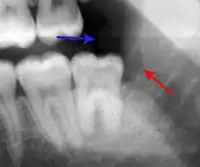

The periodontal ligament becomes inflamed and there may be pain when biting or tapping on the tooth. On an X-ray, bone resorption appears as a radiolucent area around the end of the root, although this does not manifest immediately.[10]: 228 Acute apical periodontitis is characterized by well-localized, spontaneous, persistent, moderate to severe pain.[6]: 125–135 The alveolar process may be tender to palpation over the roots. The tooth may be raised in the socket and feel more prominent than the adjacent teeth.[6]: 125–135

- Radiographs utilized to find dental caries and bone loss laterally or at the apex.